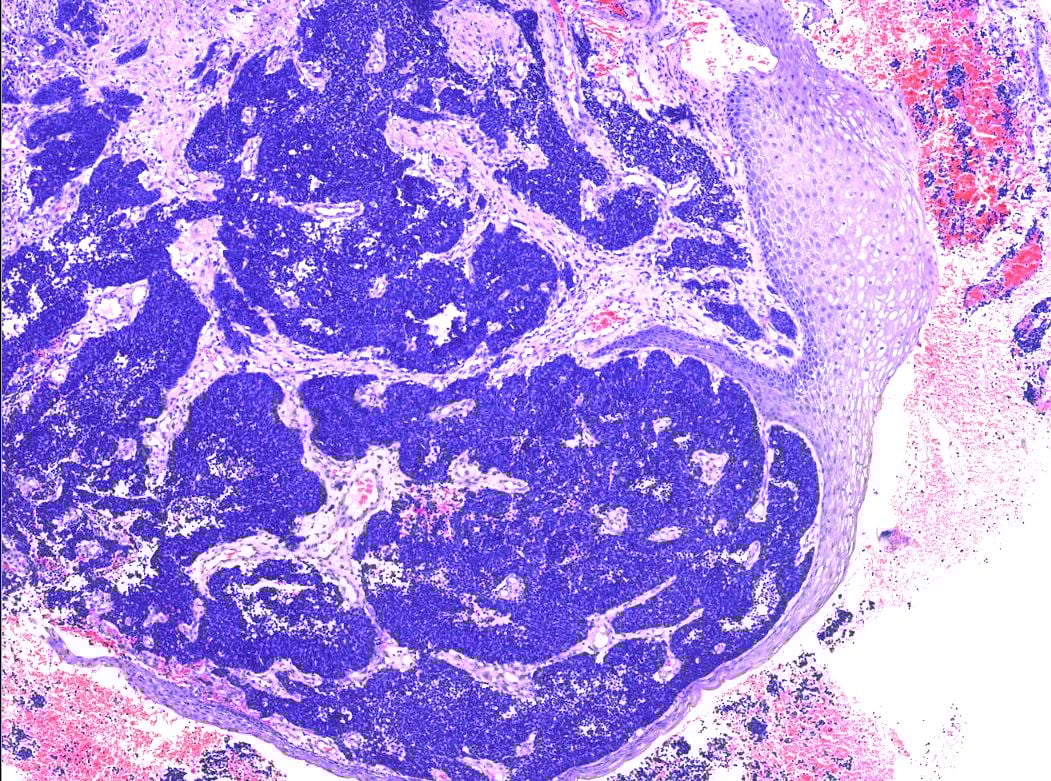

在显微镜下,肿瘤细胞位于正常的宫颈鳞状上皮下方,呈弥漫性浸润生长。这些细胞小而一致,细胞核大、细胞质少(高核浆比),核深染,排列成实性片状、巢状或梁状。此外,可见大量核分裂象和围血管生长,这些都是肿瘤侵袭性强的表现。

肿瘤位于正常宫颈鳞状上皮下方。

弥漫性浸润宫颈间质,呈实性片状,巢状及梁状排列,可见围血管生长。